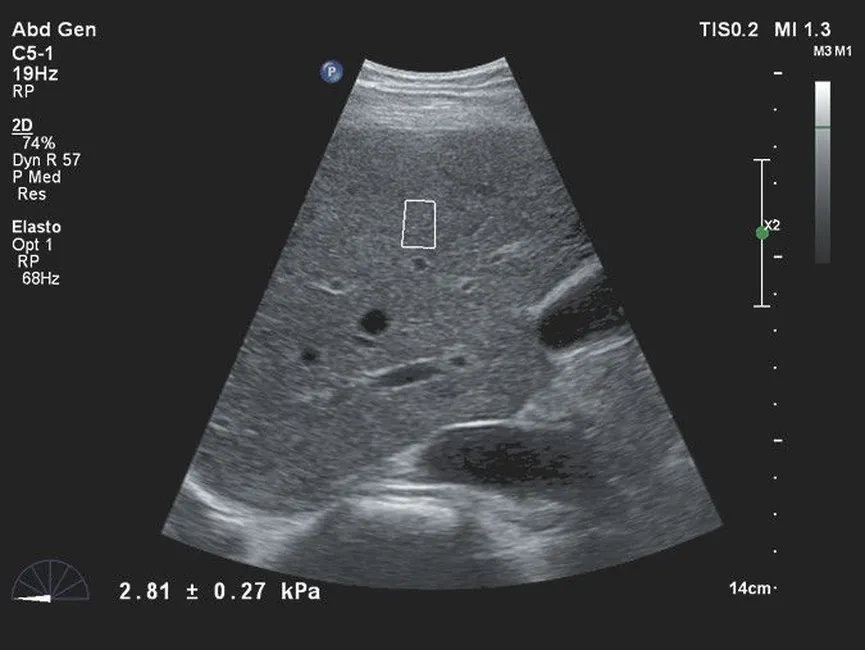

- Поддержка эластографии сдвиговой волной для количественной оценки жесткости тканей при обследовании печени, щитовидной железы и других органов.

| Эластография сдвиговой волной | Количественная оценка жесткости тканей с построением карт эластичности. |

| C5-1 | 1–5 | PureWave конвексный датчик | 160 | Абдоминальные исследования, акушерство, гинекология, исследования у пациентов с повышенным индексом массы тела |

- Абдоминальная диагностика (печень, желчные пути, поджелудочная железа, селезенка, почки).